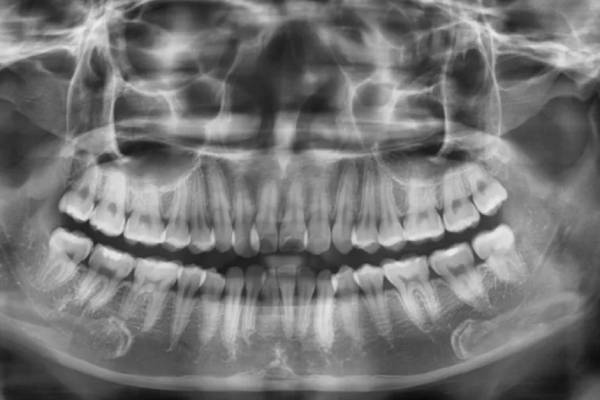

Để niềng răng một cách hiệu quả và an toàn, đầu tiên cần tìm hiểu lựa chọn nha khoa uy tín để thăm khám, chụp X quang và được tư vấn phác đồ điều trị phù hợp. Sau đó sẽ được thực hiện vệ sinh khoang miệng, lấy dấu hàm, thiết kế mắc cài hay khay niềng phù hợp với từng tình trạng mỗi người. Đối với một số trường hợp bị viêm nha chu, sâu răng,... sẽ được điều trị khỏi hẳn rồi mới bắt đầu niềng để đảm bảo hiệu quả tốt nhất.